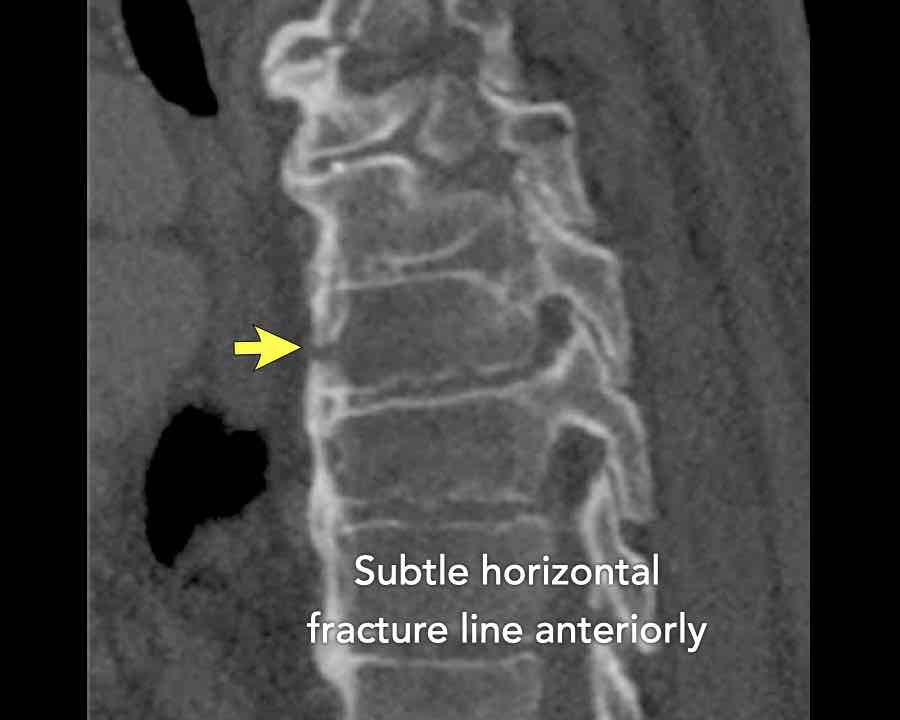

Scroll through images.

What are the findings?

Findings

- C injury? No.

- Signs of a rigid spine?

Yes, so be aware of potentially very subtle B3 injury. - A subtle fracture on the anterior vertebral body is seen (arrows).

Conclusion

Injury type B3.